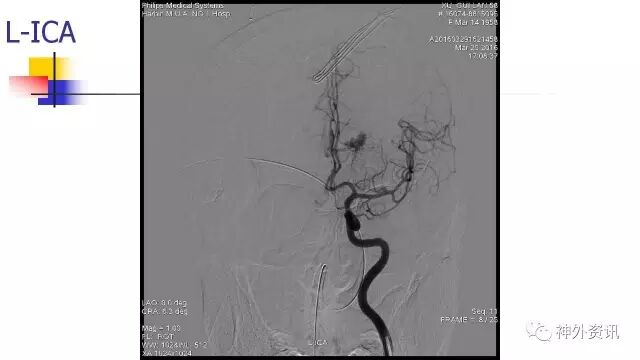

L-ICA动态